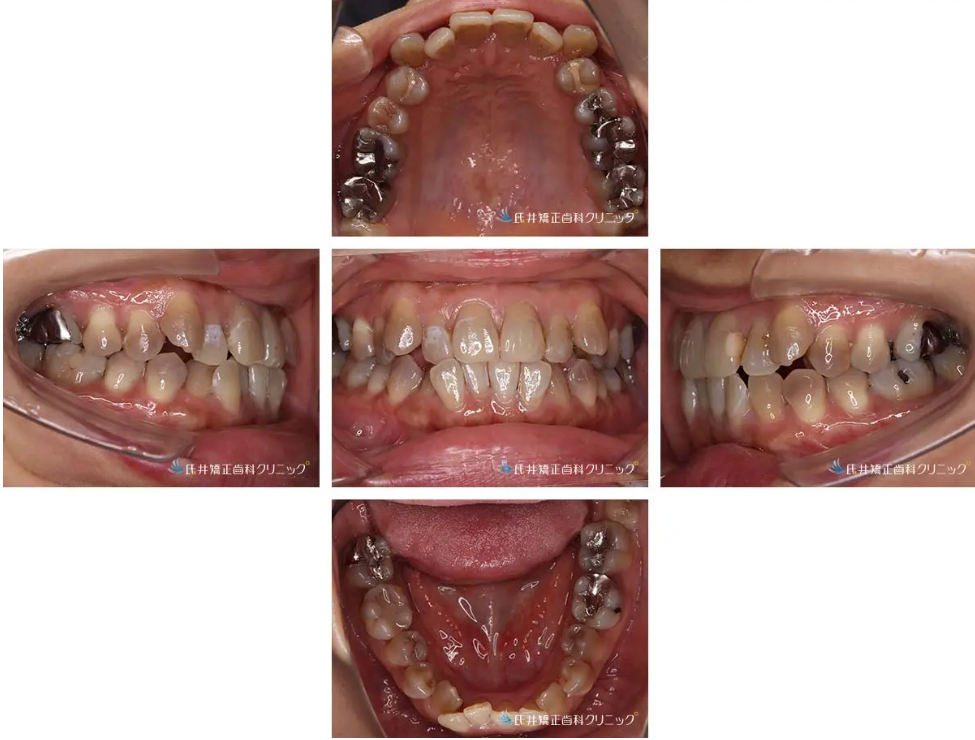

拝見すると、上の犬歯がやや外側に出ており、前歯部に**叢生(ガタガタ)**が見られました。

また、上下の真ん中(正中線)にも少しズレがありました。

3Dスキャンデータから歯並びを詳しく分析すると、上・下ともに前歯のガタつき(叢生)が明確に認められました。

特に上顎の犬歯がやや外側に位置し、下顎前歯は重なりが強い状態です。

また、上下の真ん中(正中線)にわずかなズレが見られ、咬み合わせも軽い前突傾向を示していました。

模型分析②:歯の幅とバランス

模型上では、上顎の歯列弧がやや狭くV字型を示し、下顎はアーチ幅がさらに小さいため、ボルトン比(歯のサイズ比)でも軽度の不調和が想定されます。

歯の傾斜を見ても、上顎前歯は唇側に、下顎前歯は舌側に傾いており、全体として軽度の上顎前突傾向が確認されました。